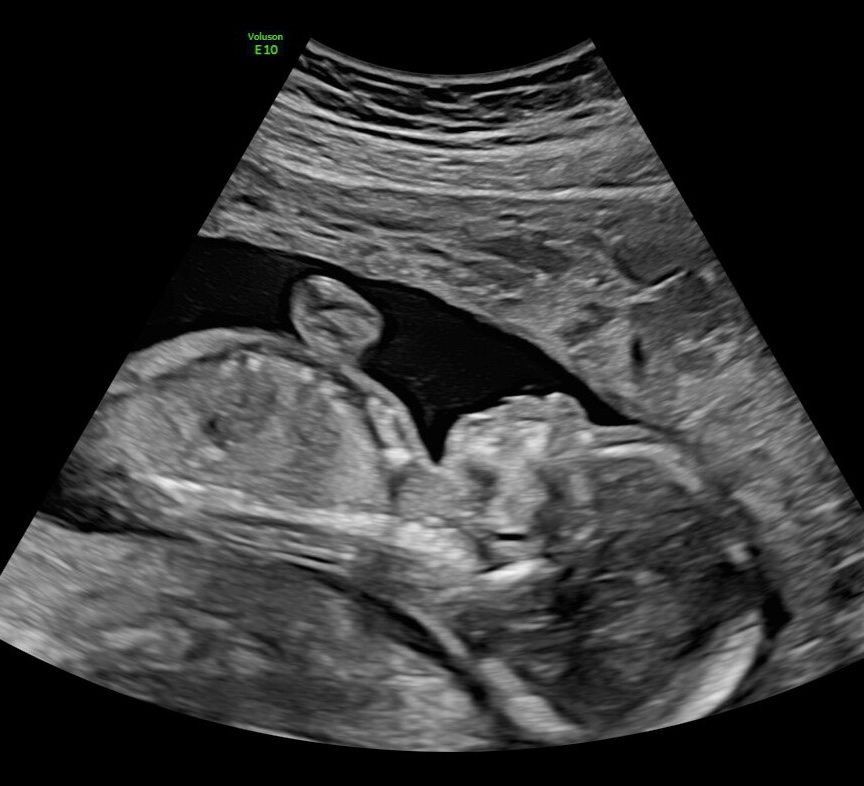

At our 12-week scan, the news was not what we expected. There were concerns. We were told to wait, to come back, to hope the next scan would tell a different story. At 16 weeks, it did not. We had more scans. We sought a second opinion. And then we heard the words no parent should ever have to hear - 'there was a global issue'.

Our beautiful boy was not growing. By 20 weeks, we were forced to make the most impossible decision of our lives. I had to deliver him.